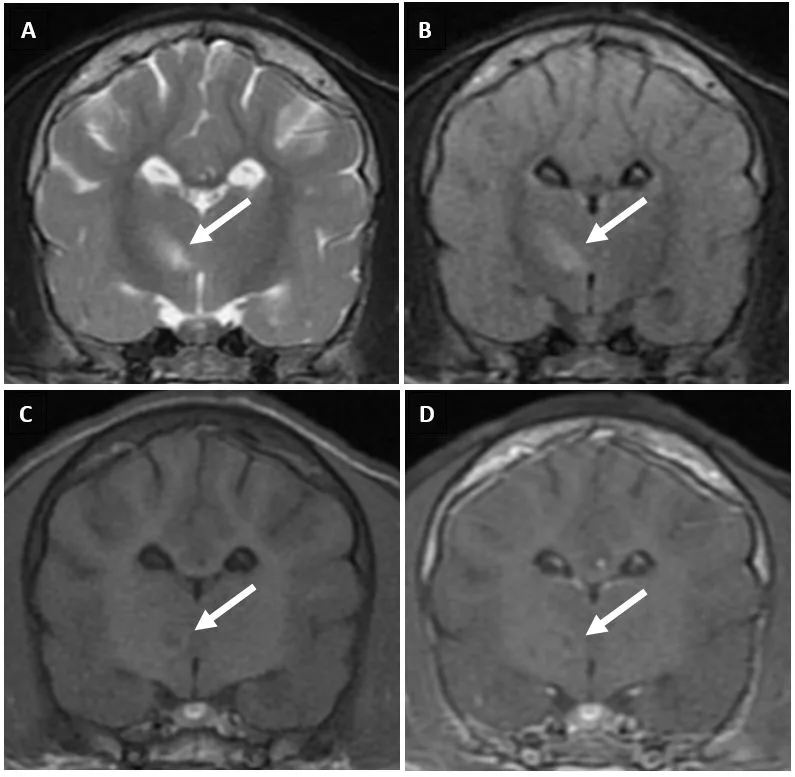

Antemortem diagnosis can be challenging and is often based on clinical suspicion alone.1 Lymphopenia, often present due to the ability of CDV to cause immunosuppression, can help raise the index of suspicion.1,8 Identifying intracytoplasmic inclusion bodies in RBCs and WBCs on a blood smear is pathognomonic (Figure 2). Inclusion bodies are only present in the acute phase of infection; thus, their absence does not rule out CDV infection.1,6,9

Cytoplasmic inclusion body (arrow) in a neutrophil on a blood smear. Cytoplasmic inclusion bodies in peripheral blood are transient and rare, occur only during the acute phase of CDV infection, and are a pathognomonic finding. Romanowsky-type stain, 1000× magnification